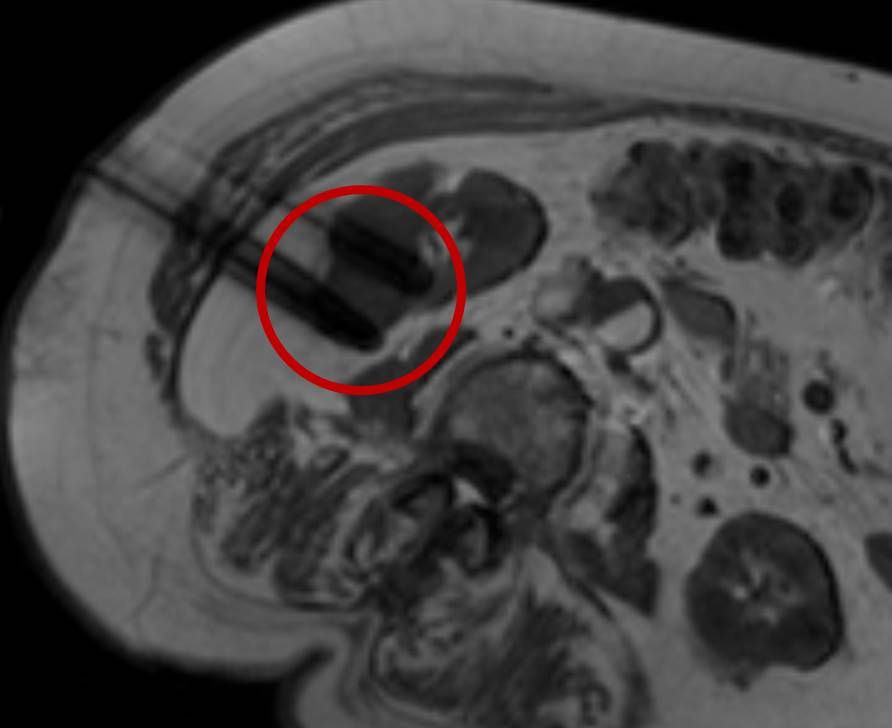

Bei der perkutanen Thermoablation von Nierentumoren werden spezielle Applikatoren unter CT- oder MRT Bildgebung in den Zieltumor eingebracht. Durch Hitze wird der Tumor zerstört.